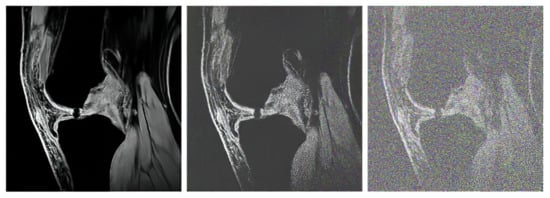

The proton density-weighted MR imaging is able to recognize in contrast the cartilage defects and abnormal cartilage composition in their tissues. This imaging sequence enables a suitable investigation of the cartilage morphology, ligaments, and menisci. The fat-saturated proton density-weighted images are suitable for the investigation of a low-signal intensities, which is a typical case of early cartilage loss. Therefore, this technique is well suited for the examination of osteoarthritis. As an example of the articular cartilage data, we provide a comparison of various sequences from the same cartilage area (Figure 4).

Proton density sequence plays an indispensable role in structural investigation of the early stage of articular cartilage loss. Here, only a weak contrast between a common cartilage surface and such pathological findings are notable. Therefore, for our analysis these data are substantially important. To objectivize such findings, we provide the example (Figure 5) from our dataset, where such investigations can be observed.